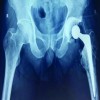

A 63-year-old male with a 1-year history of left-sided radiculopathy presented with bilateral neurogenic claudication and localized pain in the upper buttocks, radiating to the posterolateral thighs. His symptoms significantly limited his walking tolerance to 20 min. Prior conservative treatments, including lumbar epidural steroid injections, facet joint ablations, oral NSAIDs, and physical therapy, provided only temporary relief. On physical examination, the patient exhibited full motor strength (Grade 5 in all muscle groups), normal muscle tone, and preserved deep tendon reflexes. Sensory function was intact bilaterally, and the straight leg raise test was negative. Plain and dynamic radiographs showed no evidence of instability or other significant abnormalities. However, MRI revealed a left-sided paracentral disc herniation at L4–5 with associated lateral recess and foraminal stenosis (Fig. 1).

The patient underwent endoscopic unilateral laminotomy for bilateral decompression (ULBD) at L4–5 with minimal facet joint disruption. Our standard surgical approach involves removing the LF up to the tip of the superior articular process, ensuring adequate decompression of both traversing nerve roots. The procedure was uneventful, with no intraoperative complications, including nerve root injury. Postoperatively, the patient’s symptoms initially resolved. However, on postoperative day 5, the patient developed new-onset contralateral radiculopathy. As symptoms persisted, a follow-up MRI at 3 months postoperatively revealed a synovial cyst at the right L4/5 facet joint (Fig. 2). After discussing treatment options with the patient, pain management with NSAIDs and gabapentin was initiated. By the 6-month follow-up, the patient reported significant symptom improvement. As the symptoms had resolved, no further imaging studies, such as MRI, were performed.